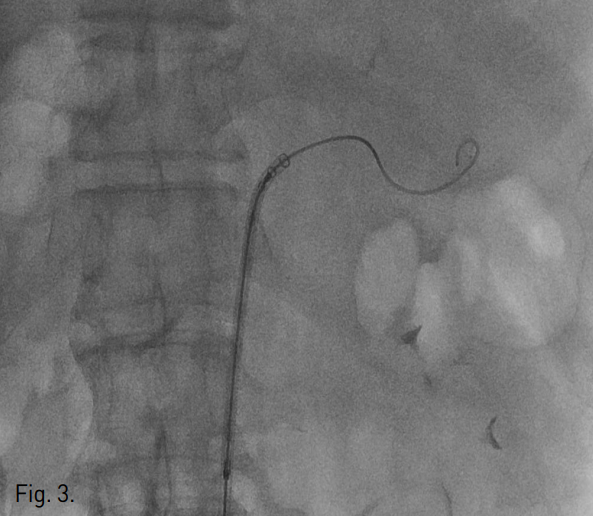

Fig. 3

Stent-graft system does not pass the tortuous course of proximal splenic artery.

복강동맥조영술에서 비장동맥 근위부에 좌위동맥 잔류부(left gastric artery stump)가 보였으며, 그 끝에서 발생한 가성동맥류가 있다(Fig. 2). 비장동맥에 stent-graft 삽입을 위하여 우측 총대퇴동맥을 통해 8F 65cm long sheath(Teleflex, 회사, USA)를 삽입하였다. Sheath의 tip을 비장동맥 근위부까지 진입시키고 Amplatz stiff guidewire(Cook, USA)를 비장동맥 원위부까지 통과시켰다. 이후 10mm × 4cm stent-graft(S&G, Korea)의 진입을 시도하였으나 stent-graft 시스템이 비장동맥 근위부의 급격한 커브를 통과하지 못하였다(Fig. 3). 총간동맥 조영술에서 잔류위를 공급하는 부위동맥(accessory gastric artery)이나 다른 측부순환로는 보이지 않아 비장동맥 색전술을 시행할 경우 위 경색(gastric infarction)이 우려되는 상황이었으나, 수술을 담당하였던 외과의와의 상의 하에 좌위동맥 잔류부를 포함하여 비장동맥을 코일을 이용하여 색전하였다(Fig. 4). 먼저 10mm × 5cm Standard coil(Cook, USA) 2개를 이용하여 frame을 형성하고 이후 8mm × 14cm Nester coil (Cook, USA) 7개를 이용하여 색전술을 시행하였다. 코일 색전술 도중 코일의 일부가 가성동맥류로 돌출하였으나 좌위동맥 잔류부를 중심으로 비장동맥의 원위부부터 근위부까지 색전하였다. 색전술 후 상장간막동맥조영술에서 미세한 측부순환로를 통해 원위부 비장동맥이 매우 약하게 조영됨을 확인하였다(Fig. 5). 시술 후 12시간에 시행한 CT 조영증강 전영상에서 위벽에 전날 시술시 사용한 조영제가 남아 있는 소견이 보여 잔류위의 관류가 매우 저하되어 있음을 알 수 있었고(Fig. 6a) 비장의 조영증강도 매우 저하되어 있었다. 그러나 동맥기 영상에서 원위부 비장동맥은 조영이 되어 보였다. 시술 7일후 시행한 CT상에서는 위점막의 조영증강은 정상적으로 보였고, 비장에도 다발성의 작은 경색 소견이 보였으나 전반적인 조영증강은 회복된 양상이었다(Fig. 6b). 환자는 시술 52일 후 정상 식이 가능한 상태로 퇴원하였다.